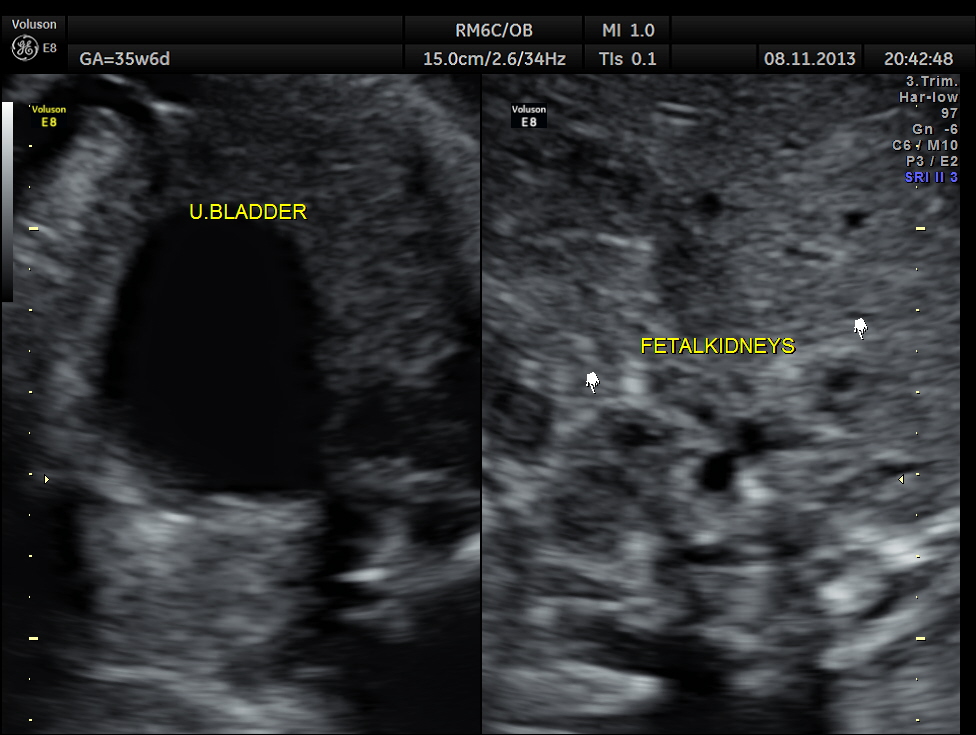

The scan was repeated at 36 weeks of gestation.

BPD, HC show < 2.3 % tile.

AC and FL appear to be normal.

the umbilical artery doppler appears normal.